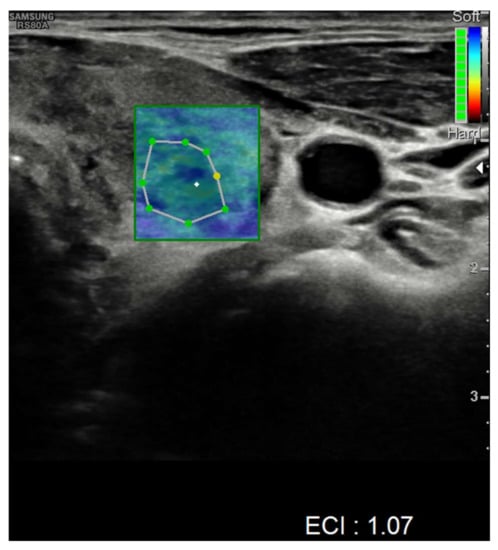

| Ultrasound findings at presentation | Asymmetric thyroid enlargement with two hypoechoic areas with no internal vascularity on right thyroid lobe | Diffuse thyroid enlargement with hypoechoic areas with heterogeneous echotexture and no evidence of increased vascularity | Diffuse enlargement of thyroid gland with hypoechoic nodules with hyperechoic shoots (micronodular pattern) without increase in vascularity | ||||||||||||||

| Ultrasonographic findings | ||||

| Hypoechoic areas | 8 (80%) | 3 (75%) | 5 (83.3%) | 1 |

| Heterogeneous echotexture | 4 (40%) | 1 (25%) | 3 (50%) | 0.571 |

| Reduced blood flow at Doppler-US | 6 (60%) | 1 (25%) | 5 (83.3%) | 0.119 |